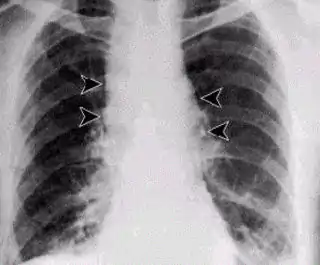

![]() Forma sistémica del carbunco: nótese el ensanchamiento del mediastino. | ||

- En la forma inhalatoria del proceso los síntomas se desarrollan rápidamente y no son específicos. Al principio se produce fiebre con toses no productivas, seguidas de dificultad respiratoria grave, con estridor, cianosis y septicemia fatal. Los rayos X muestran una expansión típica del mediastino, la muerte ocurre en un corto período en casi todos los casos.[3]